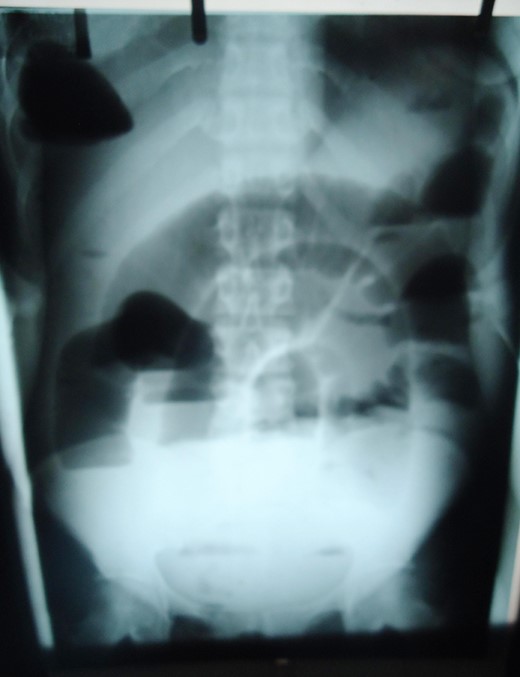

Plain abdominal X-ray showing distended small bowel loops and right sub-diaphragmatic shadow with air fluid levels from trapped bowel.

Small intestinal volvulus presents with severe colicky abdominal pains and vomiting that is difficult to differentiate from non-strangulating causes of intestinal obstruction. Early diagnosis and operative intervention is important to prevent gangrene seen in more than 40% of cases [3]. Mortality rates of 5.8–8% increases to 20–100% with gangrene [7]. Abdominal CT especially Multidetector CT with angiography is the most specific investigation [8]. Doppler ultrasonography showing the whirlpool sign is useful but operator dependent [9]. Plain radiography is insensitive in most cases. The plain radiographs of our patient showed a significant gas shadow below the right hemi-diaphragm that was discovered to be from entrapped bowel between the liver and diaphragm. An abdominal CT though more specific was omitted to minimize delay in the management. Radiological sign of hepato-diaphragmatic interposition of bowel loops was first described by Demitrus Chilaiditi in 1910 but the appearance in this patient differs from previous descriptions. Cases of Chilaiditi's syndrome have been reported in association with Fitz-Hugh-Curtis syndrome in large intestinal obstruction but none with small intestinal volvulus [10]. Treatment of small intestinal volvulus is derotation of the affected loop when viable and resection of gangrenous segments. Associated anatomical abnormalities are corrected by closure of intra-peritoneal defects, adhesiolysis or excision of mass lesions.